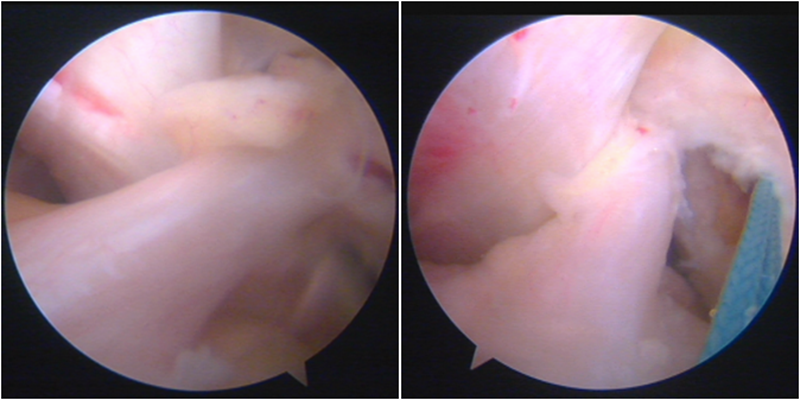

典型病例,张X,男,18岁,因扭伤致左膝关节疼痛伴活动受限1月余入院。

诊断:1.左膝前交叉韧带损伤;2.左膝外侧半月板损伤合并囊肿。

手术方案:左膝关节镜下清理、滑膜切除、外侧半月板部分切除成形、前交叉韧带重建术。

镜下显示ACL残束

内侧半月板

外侧半月板